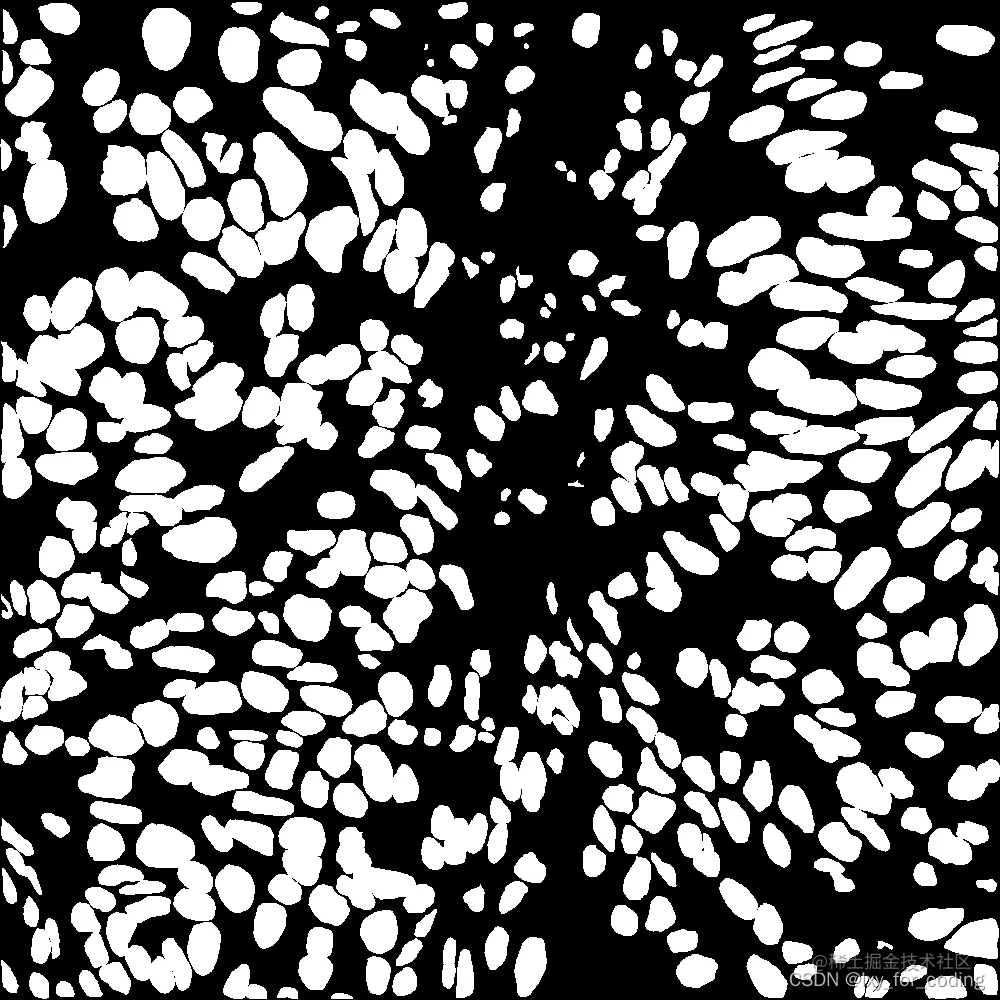

实验数据集示例:

在这里插入图片描述(标注)

在这里插入图片描述